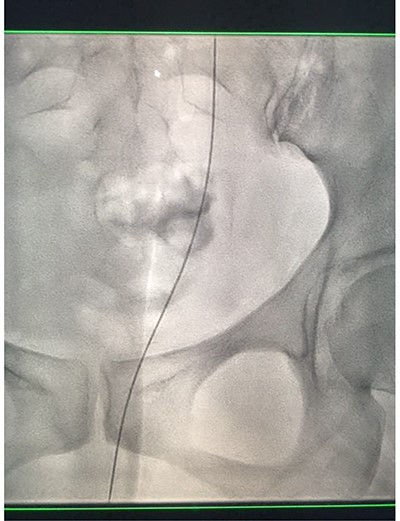

Under conscious sedation, using the previously inserted right percutaneous nephrostomy, antegrade access was achieved into the intrarenal collecting system and then into the proximal ureter. An 8 Fr × 11-cm access sheath was introduced. A guidewire was advanced antegradely through the site of ureteric transection and coiled in a position adjacent to the position of the guidewire that had been inserted retrogradely. A Gooseneck snare catheter was then passed over the guidewire and the snare was inserted (Figs 4 and 5). Under fluoroscopic guidance, the retrograde wire was retrieved and brought externally via the nephrostomy site, achieving through-and-through wire access (Figs 6 and 7).

Fluoroscopic images showing the retrograde wire successfully retrieved and brought externally via the nephrostomy site, achieving through-and-through wire access.